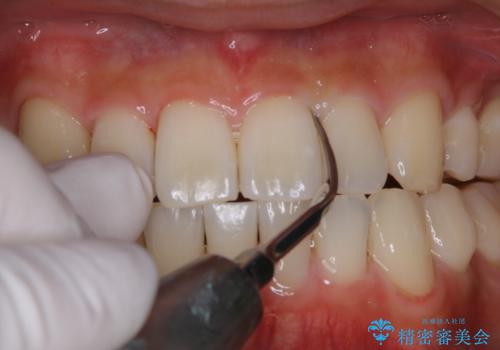

PMTCでコーヒーによる着色を除去。

PMTC(30分コース) 担当衛生士 進藤

歯の着色だけでなく、汚れもとれ歯の表面がツルツルになったと

喜んでいただけました。